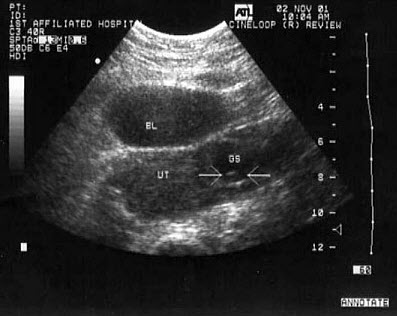

41、单项选择题

女性,27岁,停经45天,阴道不规则出血1周余。尿妊娠试验阳性。结合超声图像,最可能的诊断为()

A.宫外孕

B.附件炎性包块

C.子宫肌瘤

D.宫腔残留

E.卵巢囊肿